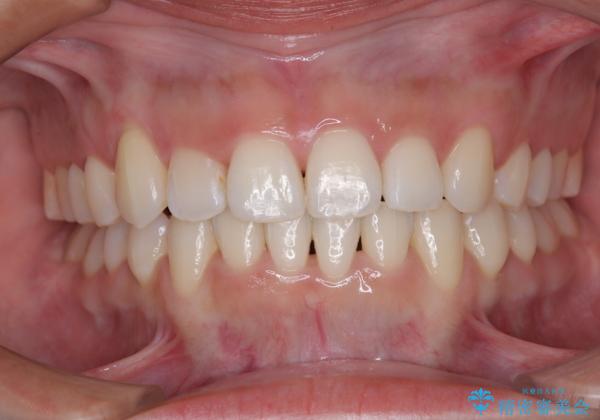

- 上下前歯のデコボコを気にして来院された患者様です。

上顎歯列が下顎の歯列に対して狭小であり、一部下顎の奥歯が上顎よりも外側に位置している状態でした。

上顎の急速拡大装置を使用して上顎骨を側方に拡大することで上顎歯列を拡大し、下顎歯列も拡大できるようにすることで、歯列を整えることとしました。